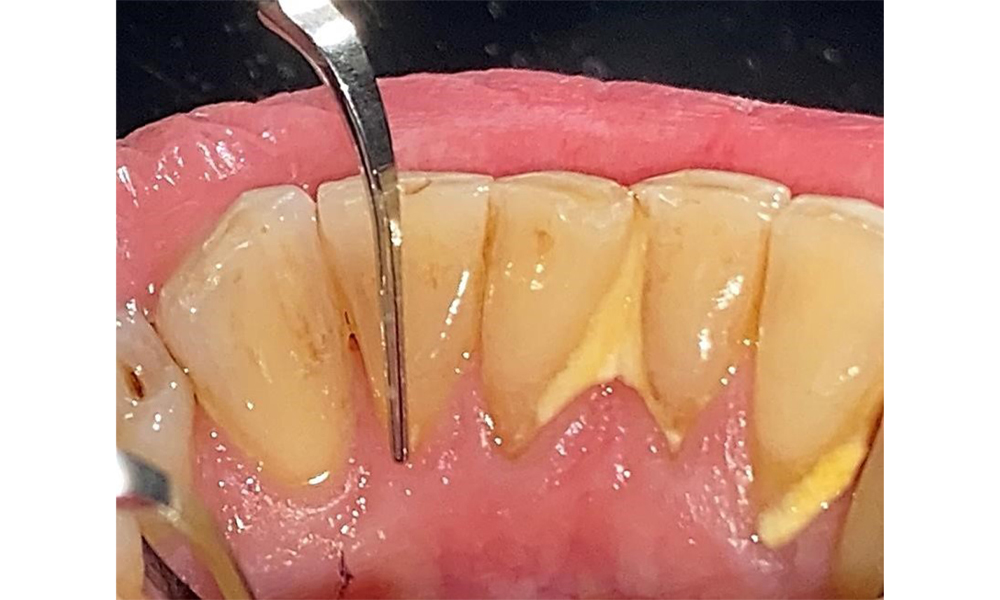

The patient has a full dentition with 28 teeth, which includes amalgam and composite fillings in the molar and premolar regions. There is a visible clinical marginal gap present on tooth 14. Tooth 27 has an adequate gold inlay. There are also generalized attritions and abrasions. (Fig. 2, Fig. 3, Fig. 4, Fig. 5, Fig. 6)

The patient has stage II, grade B periodontitis (5). At 1 to 3 mm, the clinical probing depths were within the physiological range. Localized probing depths of 5 mm were observed on the mesiopalatal aspects on both 17 and 27. There are generalized recessions of 1–3 mm with partial loss of the interdental papillae (Fig. 2, Fig. 3, Fig. 4)

The patient uses interdental brushes and an electric toothbrush. This demonstrates good compliance and good intraoral hygiene behaviour and understanding at home. Regular motivation and re-instruction are indispensable due to the risk of progression, particularly with regard to the cleaning of interdental areas, since increased probing depths were detected in these areas. Localized calculus and soft plaque was present in the lingual anterior mandibular region, and these must be shown to the patient. The interdental brush size may need to be checked and adjusted. A soft brush attachment is recommended based on the presence of exposed root surfaces to prevent wedge-shaped defects. Toothpaste with a low abrasive value should be used.